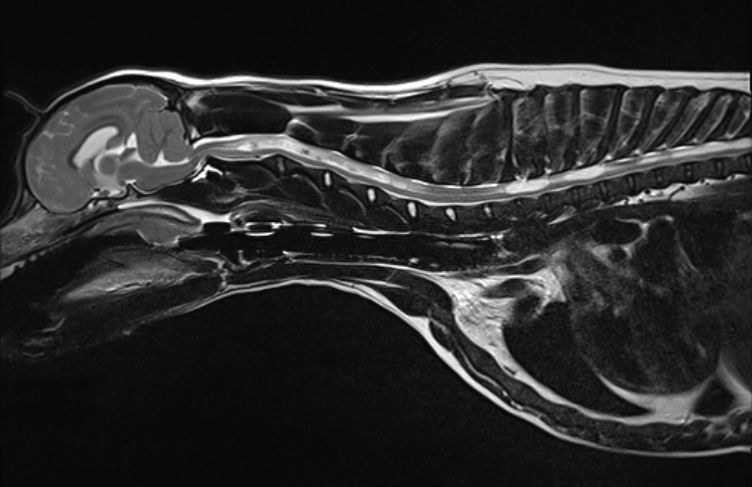

MRI image of a dog’s brain and cervical spine showing Chiari-like malformation and syringomyelia.

MRI is the gold standard for diagnosing Chiari malformation and syringomyelia in dogs. Photo courtesy: Fitzpatrick Referrals

• Visualize cerebellar herniation and crowding at the foramen magnum

• Detect syrinx formation throughout the spinal cord

• Assess the degree of ventriculomegaly, medullary kinking, and atlanto-occipital overlap

• Evaluate CSF flow disruption, which is key to understanding clinical progression

We often recommend imaging both the brain and the full cervical spine. In some cases, full spinal cord imaging may be warranted, especially if syrinxes are suspected caudally.